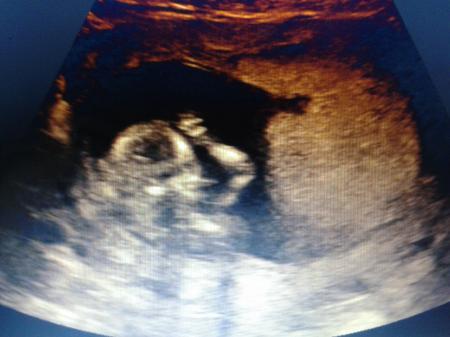

Alles super das baby ist zeitgerecht entwickelt Wir haben eine cd mit Videos und bildern mit bekommen für 5 € :) Und man konnte noch nicht sehen was es wird Vielleicht In zwei wochen zur untersuchung beim Frauenarzt Die bilder sind aus der cd hab die abfotografiert vom Laptop

Bild zu zurück von der nfm - Forum für August - Mamis

da guckt es gerade in die kamera ;)